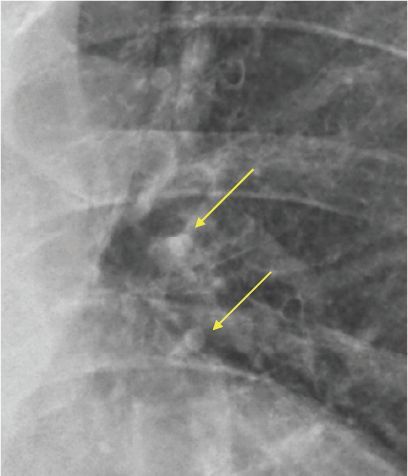

1.兩肺纖維化改善

2.左肺門附近結節變小

3.血氧濃度 >95%